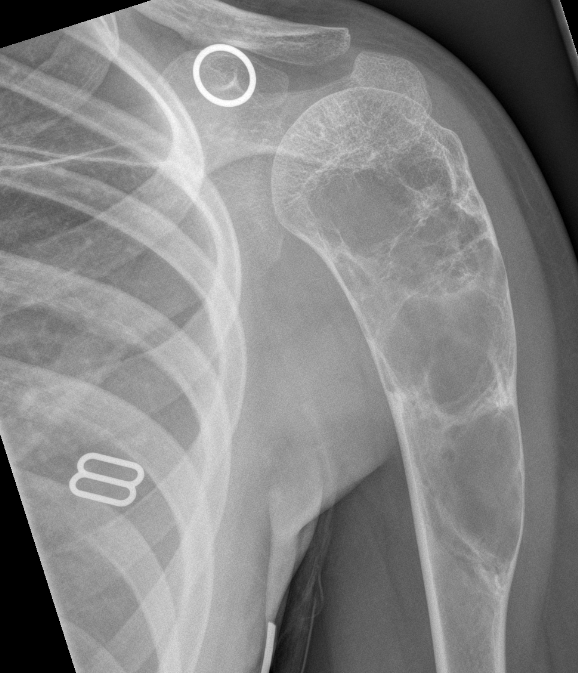

3. Aneurysmal bone cyst of proximal humerus